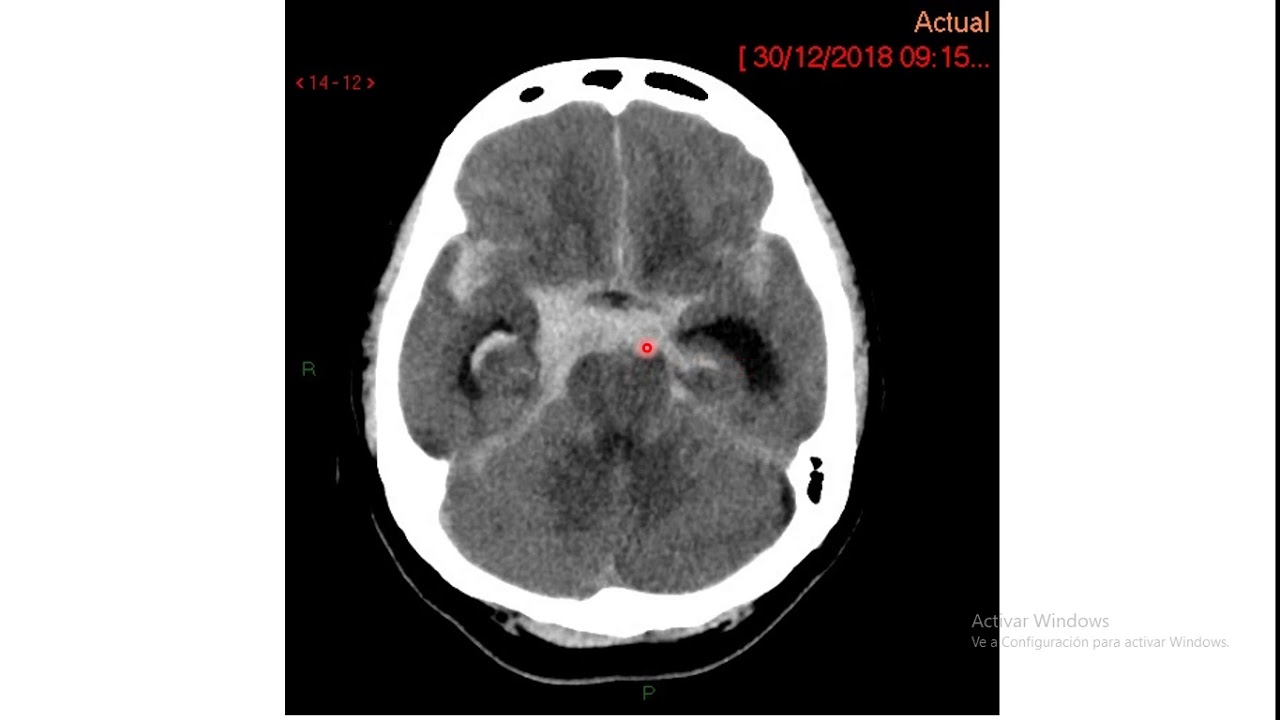

nenhum coma [Música] no item 2 nós vamos testar a motricidade ocular do paciente o quadro analisado no haiti é testar somente a motricidade ocular horizontal se o paciente estiver consciente você pede o paciente olhar os dois lados e se o paciente estiver inconsciente ou tiver uma paralisia aparente olhar você vai usar manobras óculos e fálica para avaliar se o paciente corrija para desvincular a manobra ou não venícius olha pra cá pra mim por favor sem mexer a cabeça olha k perfeito se o paciente apresentar uma aparente paralisia no olhar um rebaixamento de nível de consciência

você pode usar a manobra óculos e fábrica para avaliar se o desvio corrigir com a manobra ou se o paciente apresenta uma outra cidade preservada para os dois lados grech neste item nós vamos pontuar de 0 a 20 o paciente que apresenta uma outra cidade conjugada do olhar normal e 2 o paciente que apresenta a paralisia do olhar conjugado porém que reverte a manobra cruz e fabrica a lógica disso é avaliar se o paciente tem uma lesão encefálica do cérebro uma lesão de tom nas lesões encefálicas mesmo que o paciente apresente uma paralisia de olhar

com julgado ela é corrigível pela manobra reflexa enquanto que as lesões de tronco essa paralisia ela não é corrigível pelo reflexo evitou costumam ser mais graves e vocês vão ver que outros itens leite lesões que sugerem leis onde tron elas vão receber pontuações maiores esse é o objetivo da gente fazer essa manobra se o paciente apresentar uma lesão isolada de um dos nervos cranianos com desvio ocular seja ele a motricidade voluntária ou a manobra óculos e fabrica você vai comprar um ponto a ponto e dois pontos somente se o paciente tiver uma paralisia dos dois